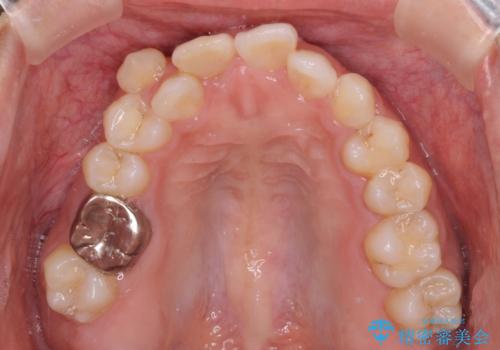

- 八重歯や前歯のデコボコを気にして来院された患者様です。

目立たない装置を希望されたので、上顎が裏側装置のハーフリンガルを選択し、上下左右の小臼歯(計4歯)を抜歯して矯正治療を行うこととしました。

裏側装置での矯正治療は、上顎前歯の正中のズレをまっすぐに改善することが難しいのですが、きれいに整えることができました。

補助装置を用いて抜歯したスペースを速やかに閉じたことで、短期間での治療となりました。